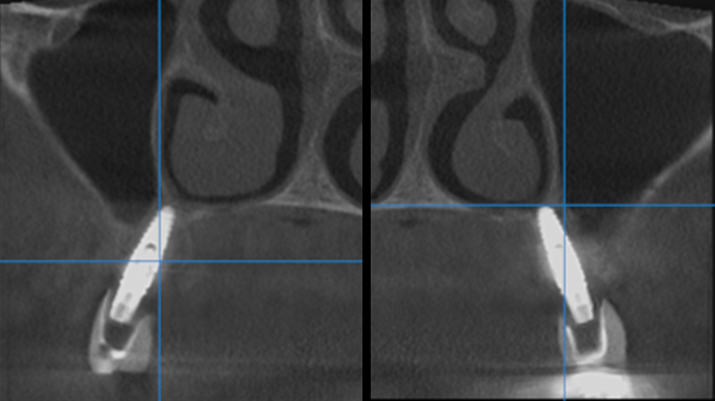

“AnyRidge shows excellent initial stability

& stable results after immediate loading in

upper fully edentulous case. ”

Clinical case: Extraction of all teeth in upper maxilla,

immediate implant placement, & provisionalization

- Courtesy of Dr. Iulian Filipov, Romania -